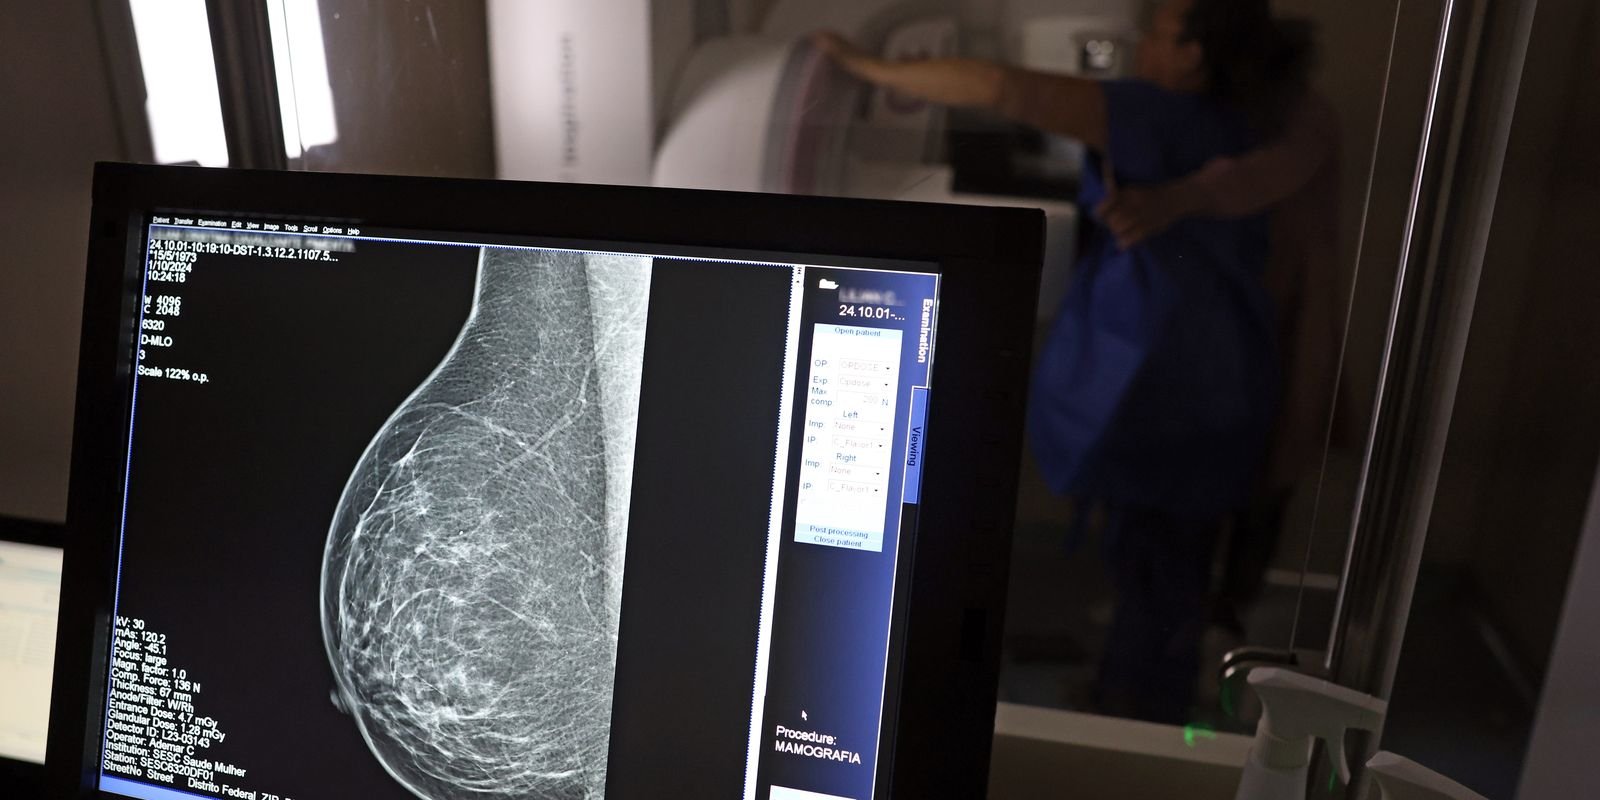

A Advocacia-Geral da República (AGU) informou nesta quinta-feira (20) ter aberto uma ação civil pública contra o médico Lucas Ferreira Mattos, por ele ter dito em postagem nas redes sociais que o exame de mamografia causa câncer de mama

O caso levou os conselhos regionais de medicina de Minas Gerais e São Paulo a abrirem investigações tendo o médico como alvo. O Instituto Nacional do Câncer (Inca) também informou, à época, não haver evidência de que a mamografia possa causar câncer de mama e que, pelo contrário, o exame previne a doença

O órgão anexou ao processo nota técnica do Ministério da Saúde segundo a qual “é recomendado que mulheres de 50 a 69 anos, de risco padrão, façam uma mamografia de rastreamento a cada dois anos. Esse exame pode ajudar a identificar o câncer antes de a pessoa ter sintomas”